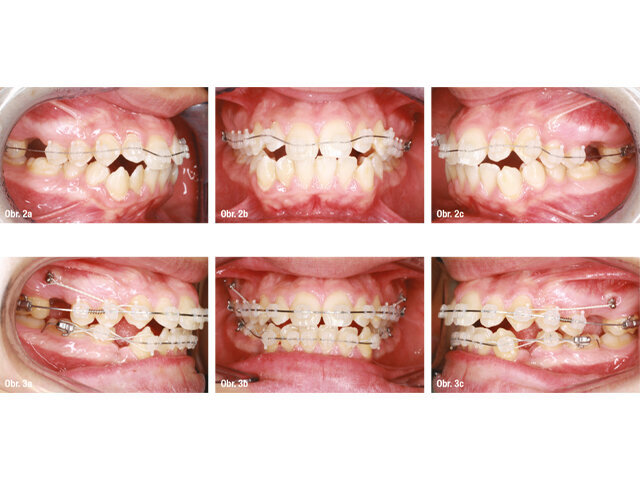

Dva týdny poté, co byly extrahovány první moláry, byly nasazeny 3M™ Clarity™ Advanced zámky s 3M™ MBT™ System preskripcí na horní čelist v kombinaci s 0.014" NiTi SE obloukem (obr. 2a–c). Nebyl použit žádný lace-back, aby nedošlo k nežádoucí mezializaci druhých molárů. Extrakce prvních dolních premolárů byly provedeny do dvou týdnů po nasazení horních zámků, ale s nasazením fixního aparátu jsme vyčkávali, aby došlo ke spontánní distalizaci špičáků. Za čtyři měsíce byly zámky nasazeny také v dolním zubním oblouku v kombinaci s lace backy a obloukem 0,014" NiTi SE; mezitím byla v horním zubním oblouku použita sekvence 0,016" NiTi SE a 0,017" × 0,025" NiTi s kotevní ligaturou od TAD ke špičákům a otevřenou pružinou mezi prvním a druhým premolárem (obr. 3a–c). Otevřená pružina vedla k distalizaci druhého premoláru a nežádoucí reciproční síla byla neutralizována kotevní ligaturou.